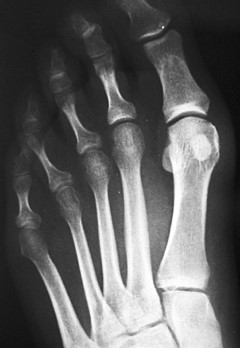

Para la corrección del hallux valgus se realizaron osteotomías abiertas, diafisaria tipo scarf o en chevron distal, con forma de “V”, y la osteotomía percutánea distal de M1 tipo Reverdin-Isham. En muchos casos se completó con una osteotomía de Akin [7] de la base de la primera falange del primer dedo del pie (Figura 4).

Figura 4a

Figura 4b

Figura 4c

Figura 4. Evolución radiográfica de metatarsalgia asociada a hallux valgas tratada con técnica de Reverdin-Isham, radiografía dorso – plantar a) preoperatoria, b) postoperatoria, c) al año de la intervención